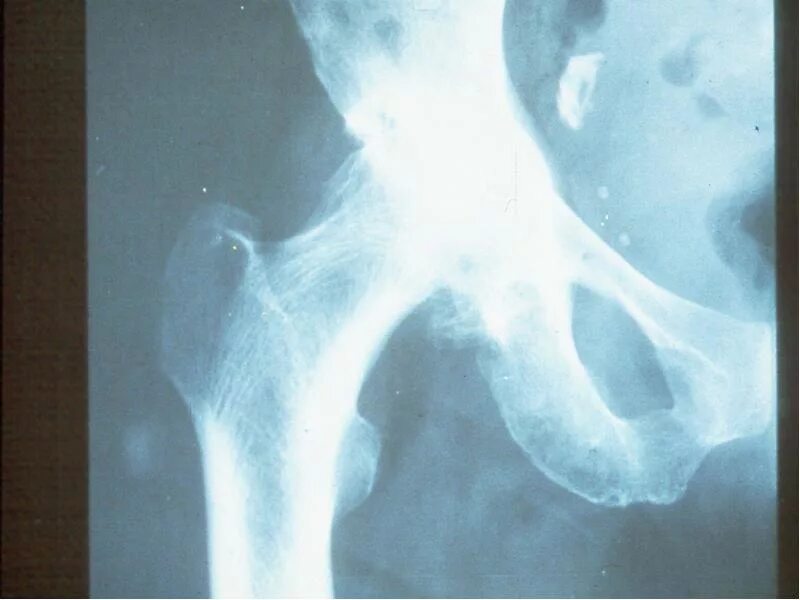

Коксартроз тазобедренного 1 стадии